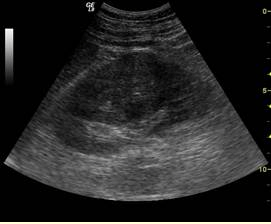

A.十二指肠闭锁

B.食管闭锁合并食管气管瘘

C.肛门闭锁

D.空肠闭锁

E.结肠闭锁